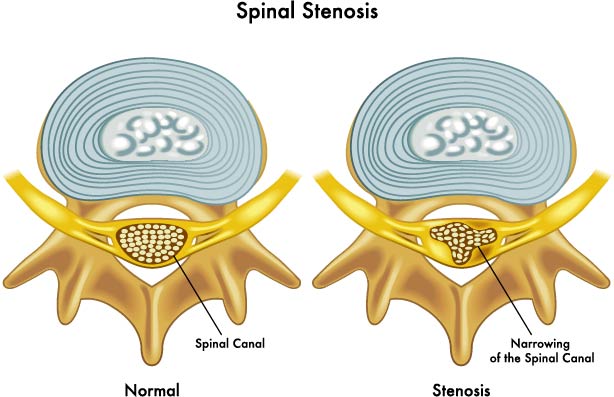

Spinal Stenosis

The illustration presents a comparison between a healthy spine and an osteoarthritic spine.

In the top half, the healthy spine is depicted with well-defined and uniformly shaped vertebral bodies. The intervertebral discs, the cushion-like pads between vertebrae, are intact and maintain a consistent height, allowing for proper spacing between the vertebral bodies. These discs are essential for absorbing shock, providing flexibility, and maintaining the integrity of the vertebral column.

In contrast, the bottom half illustrates an osteoarthritic spine. Osteoarthritis is characterized by the breakdown of cartilage and can affect any joint, including those in the spine. The vertebral bodies show signs of bone spurring, also known as osteophytes, which are bony projections that form along joint margins. These growths can occur as a natural response to the increased pressure on the degenerating cartilage and can contribute to the stiffness and pain commonly associated with osteoarthritis. Additionally, the intervertebral discs are narrowed, indicating disc degeneration. This narrowing can lead to reduced flexibility, potential nerve compression, and changes in the structure and stability of the spine.

Overall, this image serves to illustrate the structural changes that occur in the spine due to osteoarthritis, highlighting the contrast between a healthy and an affected vertebral column.